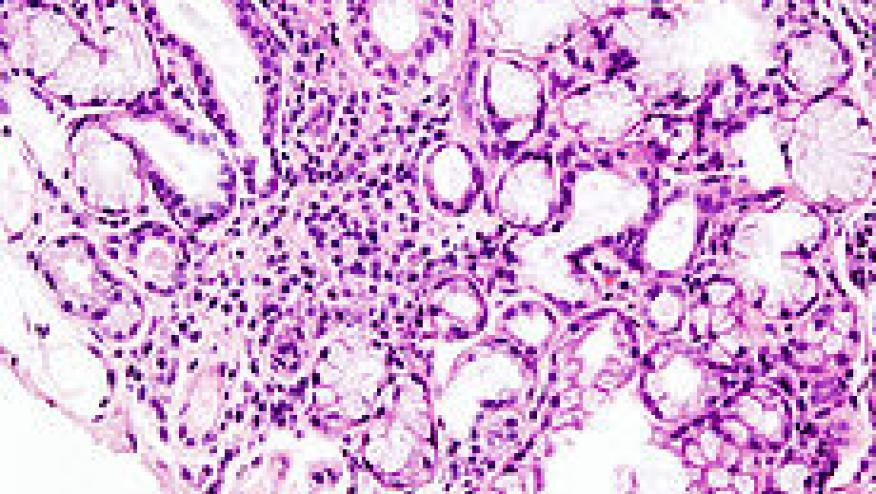

The population prevalence of Sjogrens syndrome is 0.2%, with an incidence of 4 cases per 100,000 per year. Sjogrens is 20 times more common in females than males.